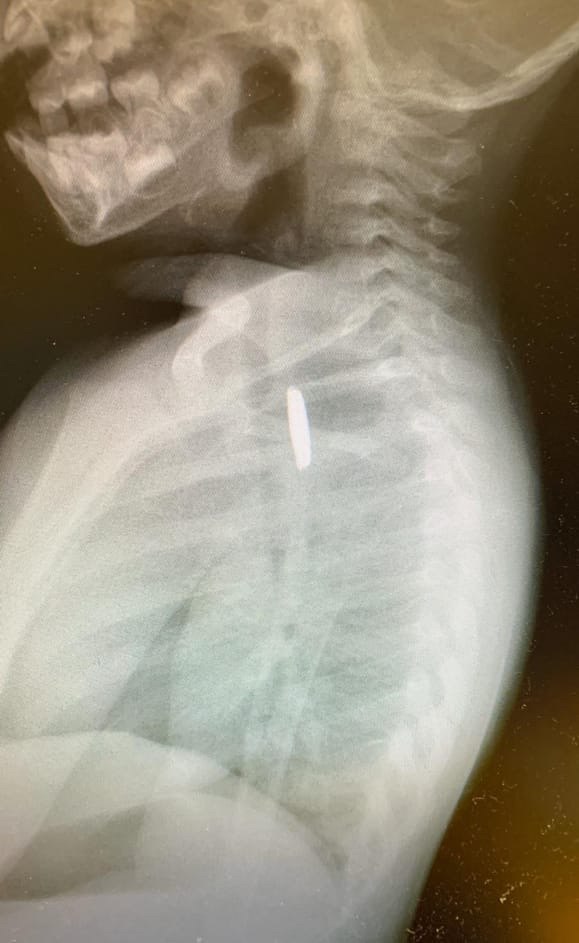

הבדיקות המקיפות כללו צילום חזה, ולהפתעת הרופאים הם הבחינו בעצם זר בצילום. לאחר בדיקה, הוברר להם כי מדובר בבטרייה (בטריית כפתור קטנה) הנמצאת לכודה בתוך הוושט של התינוק.